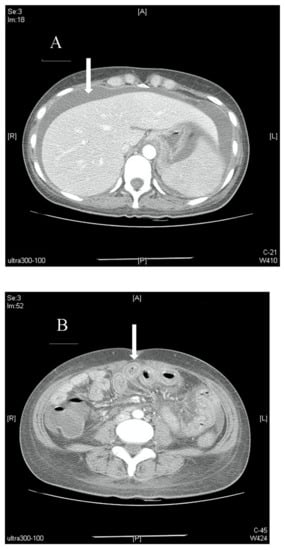

Our patient, a 28-year-old lady with no prior medical illnesses, presented to our ED with a one-day history of persistent, diffuse, dull abdominal pain associated with nausea, vomiting, and watery stools. Physical examination revealed that she was tachycardic (pulse rate 115 beats/min) and slightly hypertensive (systolic blood pressure 143 mmHg), but otherwise not tachypneic nor febrile. There was generalised abdominal tenderness without any rebound tenderness. Laboratory investigations demonstrated leukocytosis with neutrophilia (white cell count 16 × 109/µL, neutrophils 86.2%) and elevated levels of C-reactive protein (21.1 mg/dL). Other blood parameters were normal. Chest X-ray found mild left pleural effusion (Figure 1). The patient was initially treated for the provisional diagnosis of infectious gastroenteritis and colitis with empirical antibiotic therapy, but her symptoms of abdominal distension and pain continued to worsen.

Figure 1.

Chest X-ray of patient showing mild left pleural effusion.